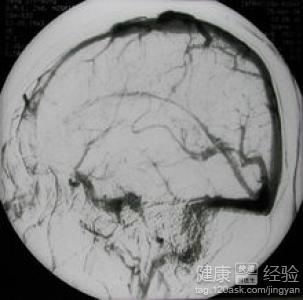

腦血管病的危險因素

腦血管病經常使患者猝然暈倒不省人事,或者伴有口眼歪斜、言語不利和偏癱等主要的表現,這些給患者帶來了很大的不便,下面介紹發病的危險的因素

1年齡和性別是很多的疾病的發病的因素的,腦血管病也不例外,常常發生在55歲以上,男性高發,有家族史的人更容易患病

2有高血壓病的患者常常會導致出血性腦血管病的發生,還可能是腦梗死,糖尿病的代謝的紊亂可以使體內的大中小血管硬化狹窄,從而導致疾病的發生,心髒病是最常見的因素